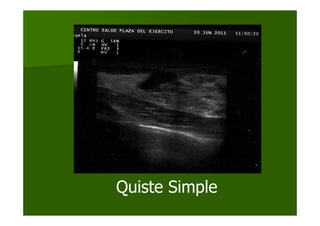

Quiste Simple

QUISTE SIMPLEQUISTE SIMPLE

–– AnecoicoAnecoico

–– Bien circunscritoBien circunscrito

–– Pared o cPared o cáápsulapsula

externa fina yexterna fina y

ecogecogéénicanica

–– Realce posteriorRealce posterior

–– SombrasSombras

marginalesmarginales

delgadasdelgadas

Se realiza ecografSe realiza ecografíía de laa de la

tumoracitumoracióón en maman en mama

derecha en la consulta dederecha en la consulta de

atenciatencióón primaria quen primaria que

mostrmostróó imagen localizadaimagen localizada

en cuadrante superioren cuadrante superior

externo, deexterno, de

aproximadamente 2,7 cm,aproximadamente 2,7 cm,

de morfologde morfologíía ovalada, dea ovalada, de

contornos lisos, bordescontornos lisos, bordes

bien definidos, con patrbien definidos, con patróónn

ecogrecográáfico anecoico, confico anecoico, con

refuerzo acrefuerzo acúústicostico

posterior, conposterior, con

caractercaracteríística ecogrstica ecográáficafica

de leside lesióón benignan benigna

sugerente de quistesugerente de quiste

simple.simple.